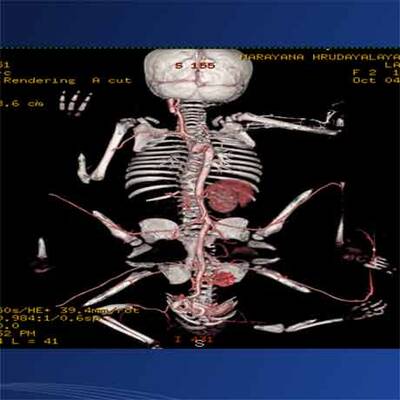

Knapp eine Woche nach einer Mammutoperation zur Entfernung von je zwei überzähligen Armen und Beinen hat sich das indische Mädchen Lakshmi am Dienstag erstmals der Öffentlichkeit gezeigt. Die Zweijährige lag im Arm ihres Vaters, hielt einen Keks in der Hand und schien gesund und aufgeweckt zu sein. Ihre Beine waren noch eingegipst. "Sie erholt sich sehr gut. Lakshmi ist jetzt nicht mehr in Gefahr", sagte Chefchirurg Sharan Patil in der südindischen Stadt Bangalore.

Sie reagiere gut auf die Behandlung und müsse daher nicht länger auf der Intensivstation bleiben, erklärte Patil. Lakshmi wurde am vergangenen Mittwoch operiert: 24 Stunden dauerte der Eingriff, 30 Ärzte waren daran beteiligt. Die Eltern des Mädchens zeigten sich danach überglücklich und erklärten, sie könnten endlich daran glauben, dass ihre Tochter ein normales Leben führen werde. Wann Lakshmi ihre Arme und Beine kontrollieren und laufen lernen kann, war aber noch unklar. Am Freitag kam das Kind wieder zu Bewusstsein. Das Mädchen habe gelächelt und die Zehen bewegt, erklärten die Ärzte. An den "neuen" Körper müsse sich Lakshmi aber offenbar noch gewöhnen.